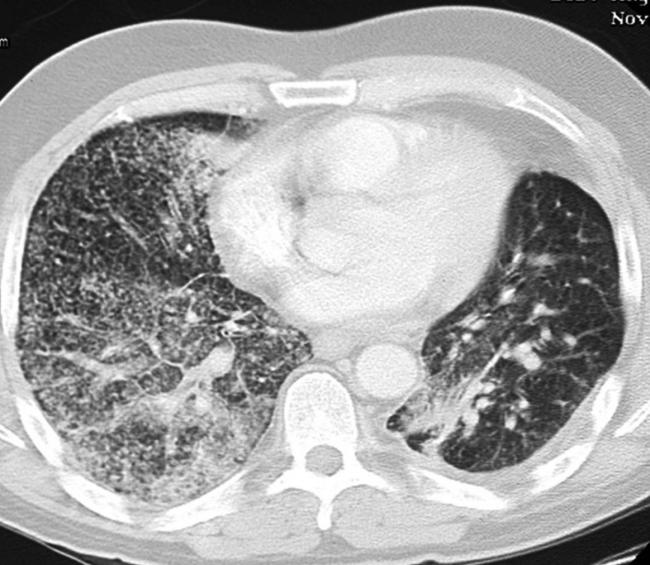

Чтобы человек несведущий смог разобраться в результатах КТ, следует знать о нюансах чтения снимков. Рассмотрим самые актуальные:

- Очаговые образования представляют собой участки белого цвета на черном фоне (на снимке-негативе). В реальности пораженная область, скорее всего, имеет более темный цвет, чем здоровые ткани легкого.

- Если врач заметит на снимке участки кальцинирования или обызвествления (капсул, пропитанных солями кальция) вокруг очага, это может быть признаком доброкачественности образования. Кальцинаты по цвету похожи на кости скелета, видимые на этом снимке. Такие явления часто обнаруживаются после затяжных простудных заболеваний, бронхитов или уже излечененного туберкулеза и представляют собой некий шрам на легких. Пациента с образованием, на котором заметны признаки кальцината, пульмонологи обычно просят раз в полгода делать контрольные снимки.

- В случае, когда образование представляет собой так называемое «облачко» или очаг по типу «матового стекла», требуется более предметное обследование. Внешне оно выглядит как затуманенная область с размытыми границами. В ряде стран пациентам с такими образованиями сразу рекомендуется операция, даже если оно не растет. Уже доказано, что в 80% случаев такие очаги являются предраковым состоянием легких. Альтернатива немедленной операции — постоянное наблюдение с контрольными снимками раз в полгода-год.

Очаговые изменения

Очаговые изменения в лёгких могут быть разного размера. Очаги мелкого диаметра 1-10 мм выявляются при различных диффузных патологиях лёгочной ткани. Очаги с высокой плотностью и довольно чётки краями в основном наблюдаются в интерстиции лёгкого. Различные очаги низкой плотности, напоминающие матовое стекло, с нечёткими контурами возникают при патологических изменениях в респираторных отделах дыхательных органов.

Нужно учитывать, что плотность и размер очагов имеет слабое диагностическое значение. Для постановки диагноза более важным может быть распределение патологических процессов в лёгочной ткани:

- Перилимфатический очаг – часто наблюдается в бронхах, сосудах, в междольковых перегородках и листках плевры. В таком случае видны неровные контуры анатомических структур, при этом перегородочки и стенки бронхов несколько утолщены, как и стенки сосудов. Подобные патологические изменения часто встречаются при туберкулёзе, силикозе, саркоидозе и карциноматозе. При этих патологиях очаги небольшие и не превышают 2-5 мм. Состоят такие очаги из гранулем или метастатических узелочков, они наблюдаются вдоль лимфатических узелков в ткани лёгких и плевре.

- Полиморфный очаг. Такие очаговые образования в ткани лёгких возникают при туберкулёзе. В этом случае КТ позволяет увидеть участки разной плотности и размеров. В некоторых случаях такая картина наблюдается при онкологических патологиях.

- Центрилобулярные очаги. Наблюдаются в артериях и бронхах или в непосредственной близости от них. Они могут быть довольно плотными, хорошо очерченными и однородными. Изменения лёгочной ткани такого типа наблюдаются при пневмониях, эндобронхиальном туберкулёзе и разных видах бронхита, преимущественно бактериального происхождения. Есть и другой тип центрилобулярных очагов, в этом случае лёгочная ткань имеет мелкие уплотнения и похожа на матовое стекло.

- Периваскулярные очаги – это патологические образования, которые находятся в непосредственной близости от кровеносных сосудов. Такое состояние наблюдается при онкологических патологиях и туберкулёзе. Очаги могут быть как единичные, так и множественные.

- Хаотично расположенные очаги. Такие образования характерны для патологических гематогенных процессов. Это может быть гематогенная инфекция, туберкулёз или метастазы гематогенного типа. Большие множественные очаги, размером около 10 мм, частенько наблюдаются при септических эмболиях, гранулематозе, грибковых инфекциях и метастазах. Все эти заболевания имеют некоторые отличия, по которым их можно дифференцировать.

- Субплевральные очаги – это патологически изменённые участки, расположенные под плеврой. Наблюдение таких участков на снимке всегда говорит о развитии туберкулёза или онкологических заболеваний.

- Плевральные очаги. Такие патологические образования расположены на плевре. Наблюдаются при воспалительных и инфекционных патологиях нижних дыхательных органов.

- Апикальный очаг представляет собой чрезмерное разрастание фиброзной ткани, которая со временем замещает здоровые клеточки.

- Лимфогенный карциноматоз. Это понятие включает два типа патологических изменений в лёгких. С правой стороны наблюдается альвеолярная инфильтрация, с видимыми просветами бронхов. С левой стороны плотность лёгочной ткани несколько повышена. В зоне уплотнения наблюдаются стенки бронхов и сосудиков.

При очаговых заболеваниях участки патологически изменённой ткани могут быть разными по размерам. Они могут быть мелкими, размером не более 2 мм, средними – диаметром до 5 мм и крупными, размер последних превышает 10 мм.

Патологические очаги бывают плотными, средней плотности, а также рыхлыми. Если в лёгких наблюдаются единичные уплотнения, то это может быть как возрастным изменением, которое не представляет опасности для человека, так и опасным заболеванием. Если наблюдаются множественные очаги, то здесь речь идёт о воспалении лёгких, туберкулёзе или редких формах онкологических заболеваний.